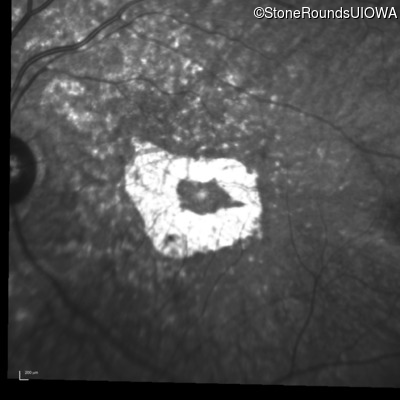

Infrared Fundus Photograph - Left - 5/600

Exemplar